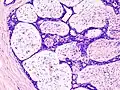

| Histopathologic image of breast fibroadenoma. Core needle biopsy. H&E stain. | |

Histopathologic image of breast fibroadenoma. Core needle biopsy. Hematoxylin & eosin stain. -